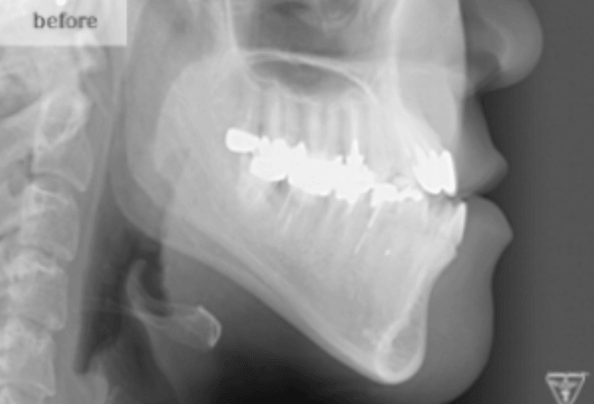

治療前